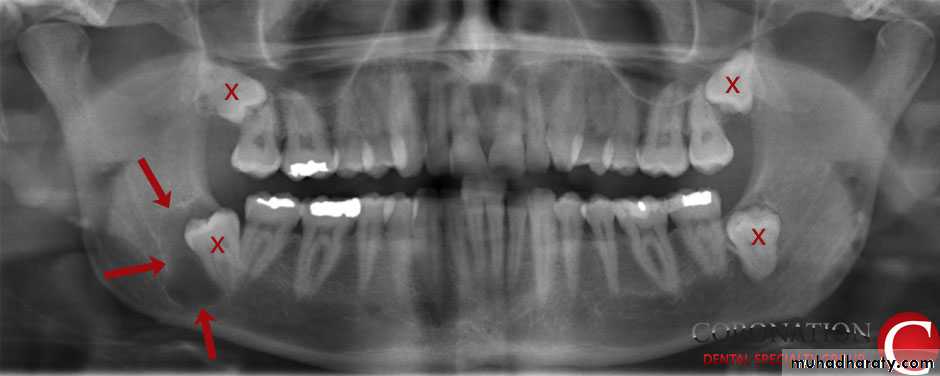

INDICATIONS OF THE TRANSALVEOLAR APPROACH

.

1-Retained roots, which can’t be grasped by the root forceps.

2• Hypercementosis of a tooth.

3.Broken teeth

4.Sclerosis of the bone

5.Teeth associated with pathology –

periapical granuloma, cyst, tumor etc6• Impacted teeth, embedded teeth

7.Any tooth, which offers a lot of resistance in forceps extraction.

8.Curved roots - Multi-rooted teeth (like molars) that have especially curved, hooked or crooked roots can be stubborn extractions. Beyond just being difficult, the act of pulling these teeth may require the use of excessive forces that may result in bone or tooth breakage